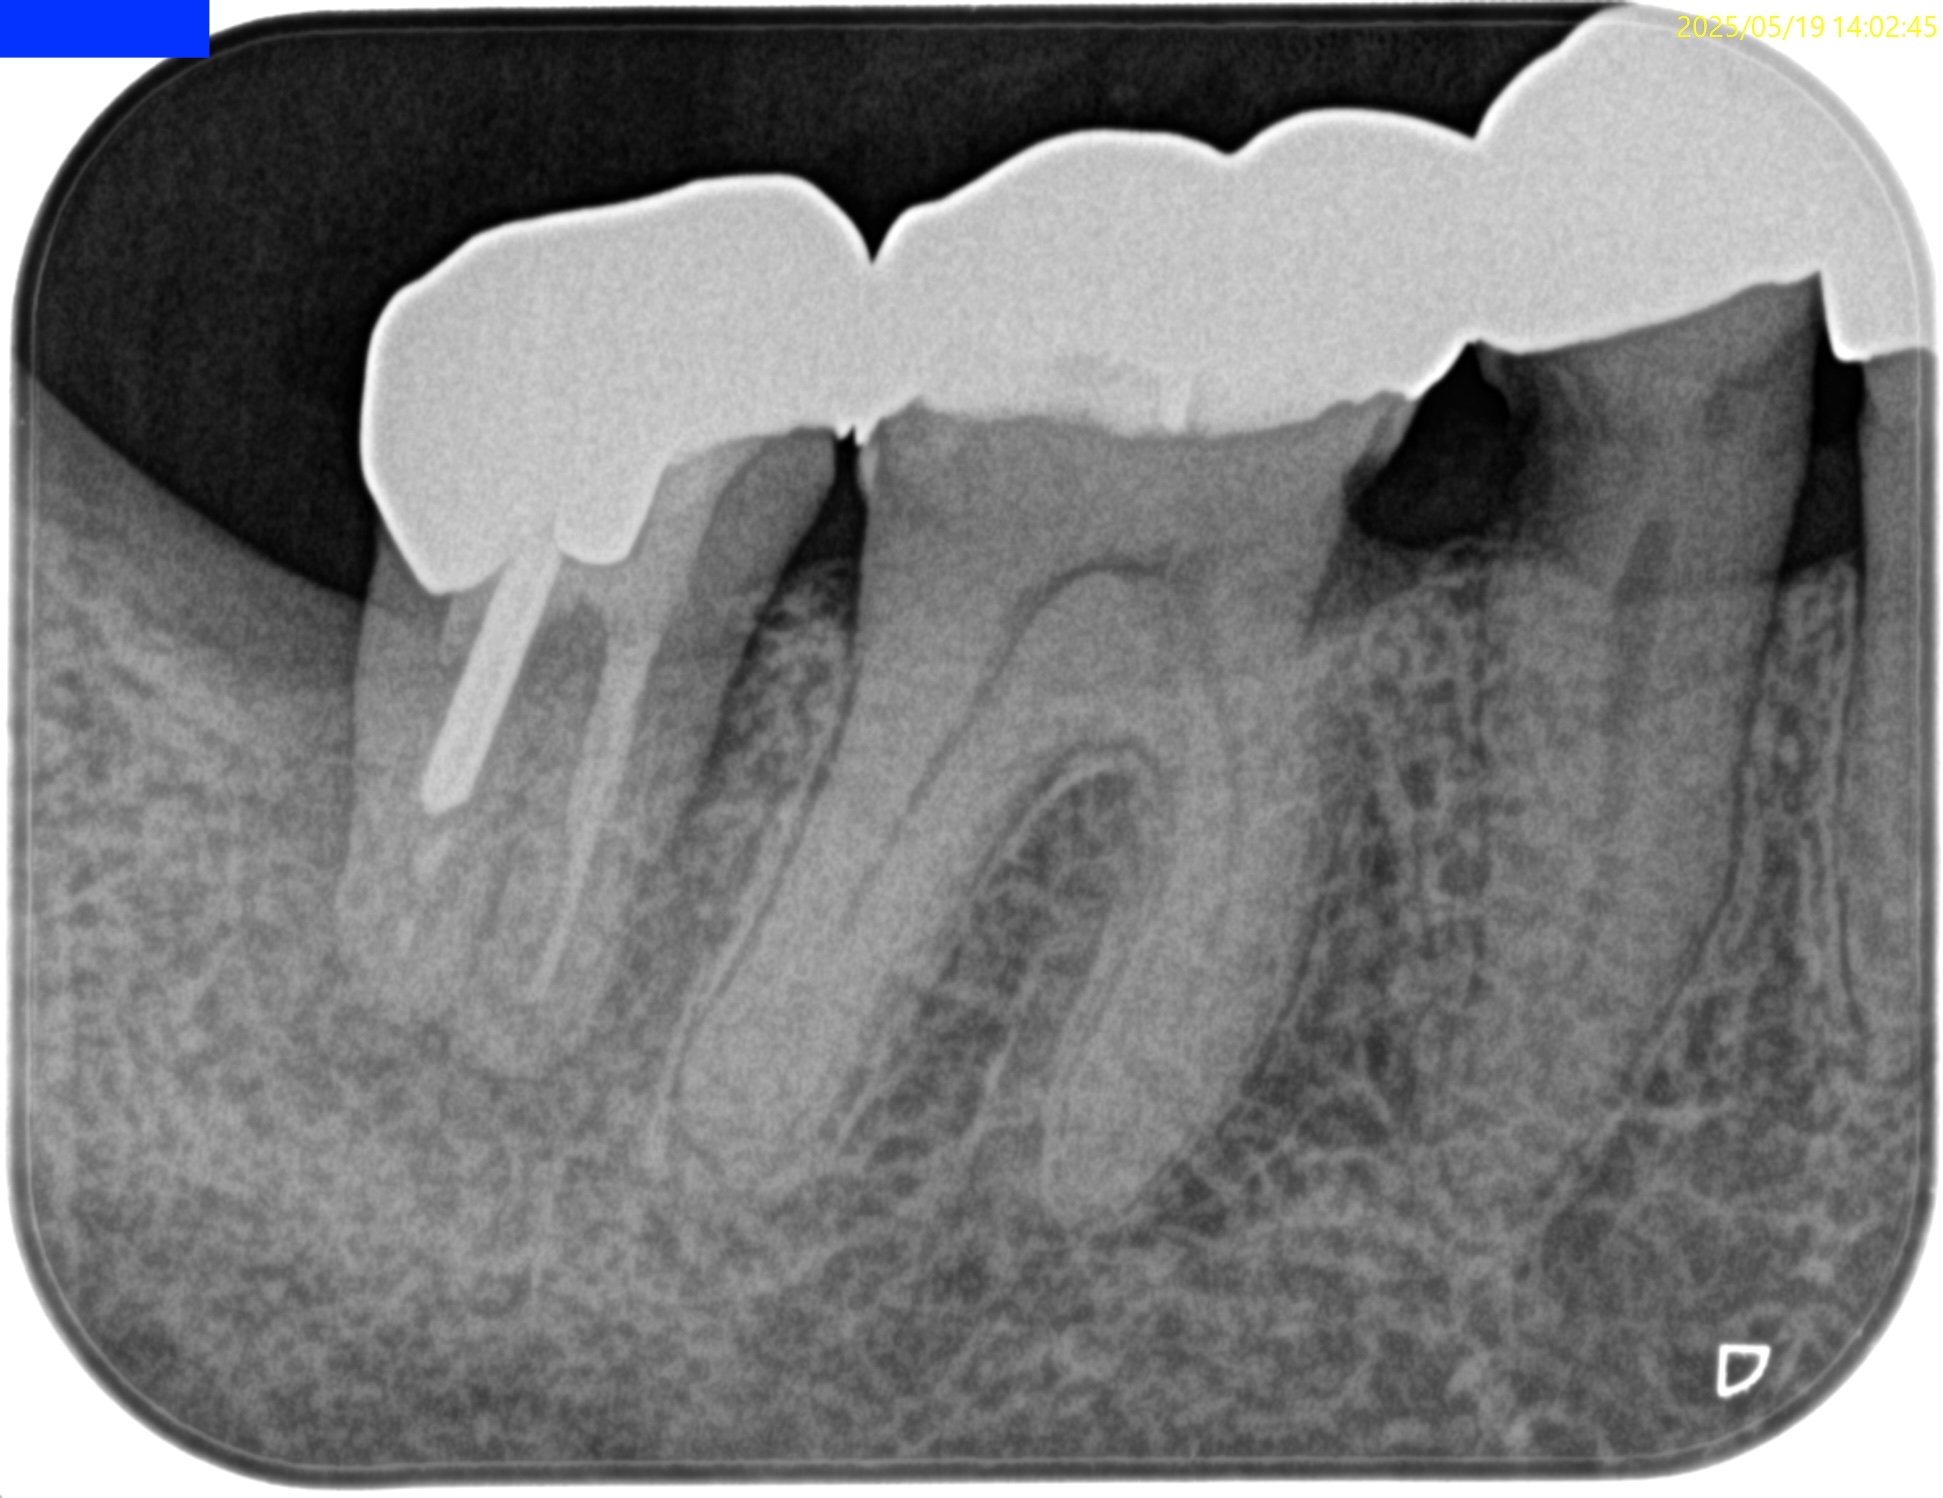

PA(2025.6.25)

検査でなく、PAで初めて患歯が#29だとわかる。

歯髄に迫る大きな虫歯が保険の修復物の下部にある。

これが保存できるだろうか?